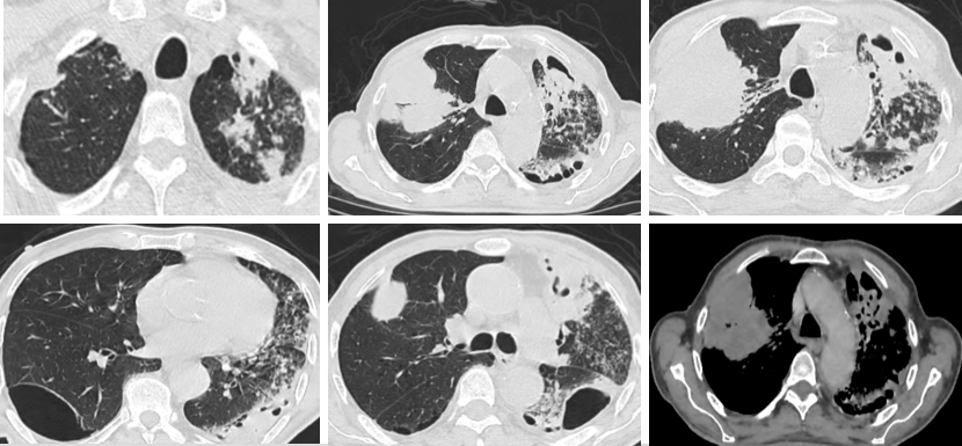

Homme, 80 ans, tabagique et hypertendu;

Installation progressive depuis 2 mois: dyspnée, toux, bronchorrhée et amaigrissement.

QUEL EST VOTRE DIAGNOSTIC ?

A – COP

B – Broncho-pneumopathie bactérienne

C – Broncho-pneumopathie bactérienne avec abcès pulmonaire

D – Tumeur bronchique avec localisation controlatérale

E – Coexistence tumeur bronchique et tuberculose pulmonaire